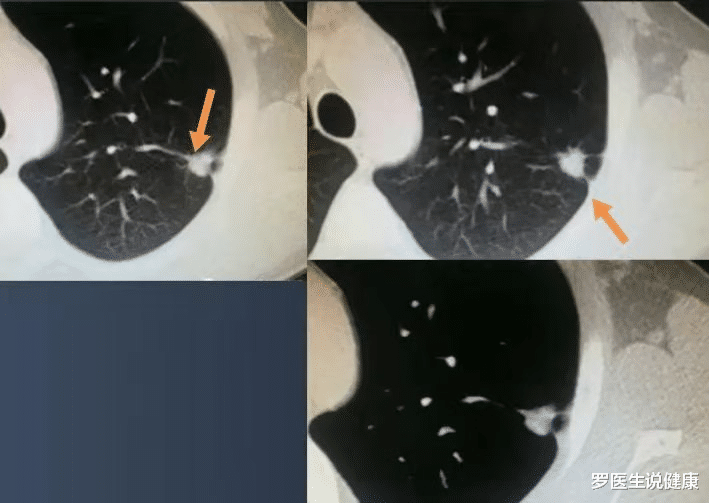

比如上图这个结节 , 靠近肺门大血管 , 但内部有多发钙化 , 像爆米花一样 , 这是错构瘤(一种良性肿瘤)的典型表现 , 不必紧张 。 这里有个小窍门:直径<2.0cm的结节 , 如果内部有钙化(白色区) , 基本都是良性!因为肺癌在小时候很少发生钙化 。

恶性肺结节的CT片长什么样?下面聊聊恶性肺结节的特点 , 随便给大家看一些有代表性的CT片子 , 很简单 。

首先按照密度 , 我们把肺结节分为三类:纯磨玻璃结节、混合磨玻璃结节、实性结节 。

1.混合磨玻璃结节恶性比例最高 , 多为肺腺癌 , 当病灶小于3厘米且实性成分<50%时 , 治疗效果最好!

像上图这种结节 , 混合磨玻璃 , 实性成分比例小于50% , 多数分化良好 , 手术可以治愈 , 并且不需要后续治疗 , 手术后定期复查就好 。

这个结节直径1.6cm , 有不规则实性成分 , 且病人比较年轻(不60岁) , 选择手术治疗 , 病理是原位腺癌 , 已治愈 , 手术后不会复发 。

上图这个病灶也是混合磨玻璃结节 , 直径也是1.6cm , 但实性成分>50% , 手术病理为低分化肺腺癌(以实性型和微乳头型生长为主) , 为降低复发风险 , 手术后打了化疗 。